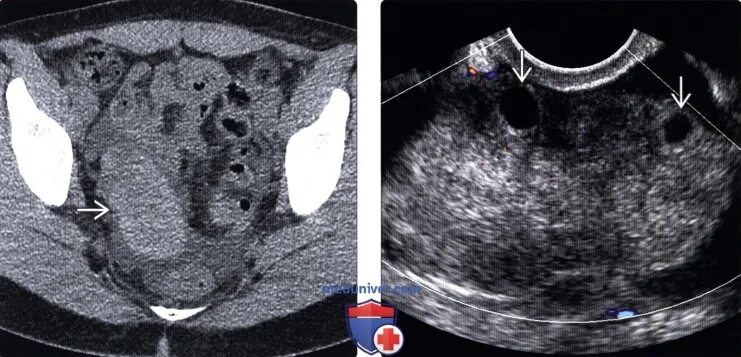

Перекрут придатков матки